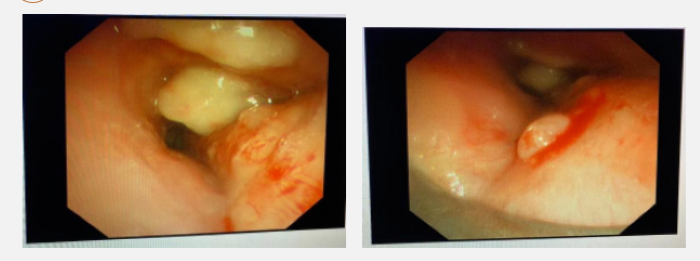

气道支架置入术中

肖祖克(中)、 吴西雅(左)、梁莹(右)在术中

肖祖克将气道金属支架释放器经硬镜送入左主支气管远端,松解绑线,金属覆膜支架释放,仅一分钟左右气道支架精准“落户”在最佳位置,李大爷的气道瞬间通畅。

气道支架置入后

术后患者生命体征平稳,呼吸困难明显缓解。伴随着这条通道的重新打开,李大爷脱离了病危风险,也为下一步肿瘤治疗争取了宝贵的时间。